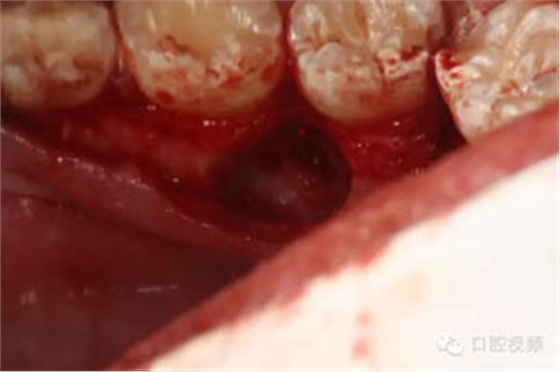

圖9.分牙、分別取出牙冠和牙根

圖11.清理拔牙創(chuàng)。

圖12.取出是埋伏牙牙根